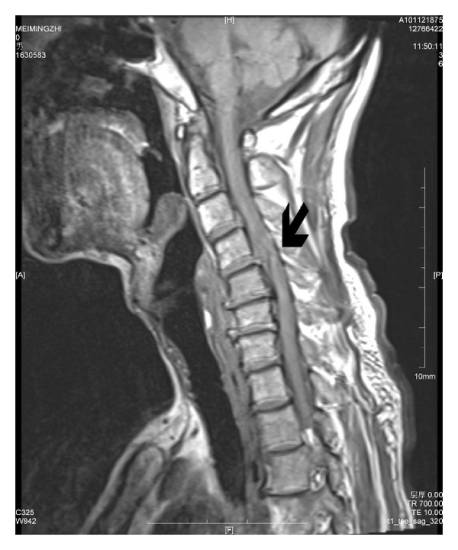

Подтвердить диагноз позволяют МРТ позвоночника, КТ, рентгенологическое исследование. Дополнительно могут исследоваться сосуды шеи путем ультразвукового исследования.

Во время диагностики врач выявляет причину заболевания, ищет сопутствующие отклонения строения и функции позвоночника, определяет точную локализацию и стадию патологического процесса.